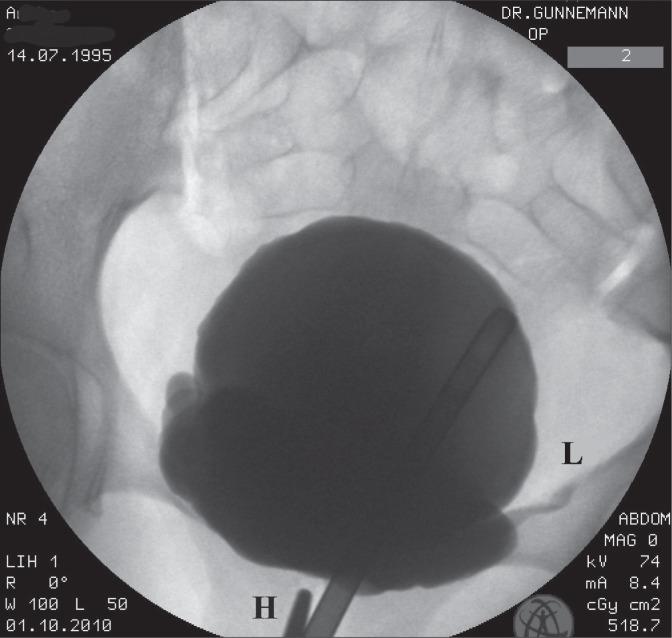

We applied unilateral midurethral pressure during a radiological investigation of a 15-year-old female patient who had undergone 2 surgeries for ureteric reflux.

On injection of the dye into the bladder, reflux was noted in the left ureter, and this disappeared within 2-3 seconds after pressure was applied on 2 successive occasions in the midurethral area of the vagina.